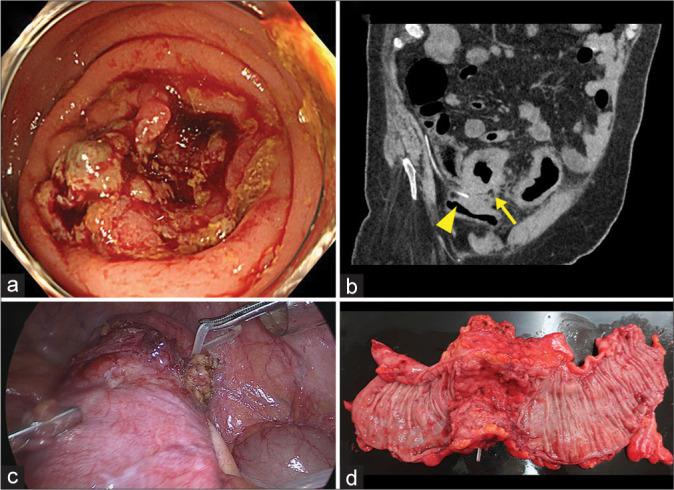

A 72-year-old man presented with a 1-month history of constipation, diarrhea, and weight loss. His medical history consisted of subarachnoid hemorrhage and hydrocephalus 13 years earlier, for which endovascular coiling and VP shunting were performed. Colonoscopy showed a sigmoid mass, the biopsy of which revealed tubular adenocarcinoma. Computed tomography demonstrated circumferential wall thickening of the sigmoid colon without evidence of metastasis, with the lesion surrounding the tip of the VP shunt. He underwent laparoscopic surgery for sigmoid colon cancer. Unexpectedly, the VP shunt was trapped in the serous side of the tumor, and both the shunt and tumor were excised. Microscopic examination revealed inflammation and fibrosis, but no cancer cells were found in the serosa surrounding the embedded VP shunt tip.

一名72岁男性,有1个月的便秘、腹泻和体重减轻病史。他的病史包括13年前的蛛网膜下腔出血和脑积水,当时行血管内栓塞和VP分流术。结肠镜检查显示乙状结肠有肿物,活检显示为管状腺癌。计算机断层扫描显示乙状结肠壁环形增厚,无转移迹象,病变围绕VP分流管尖端。他接受了乙状结肠癌的腹腔镜手术。出乎意料的是,VP分流管被困在肿瘤的浆膜侧,遂将分流管和肿瘤一并切除。显微镜检查显示有炎症和纤维化,但在嵌入VP分流管尖端周围的浆膜中未发现癌细胞。